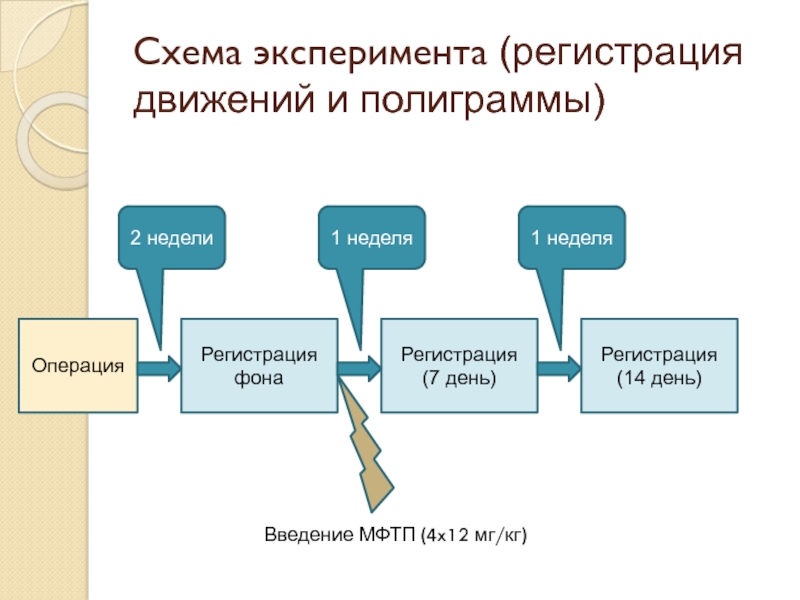

- 17. Схема эксперимента (регистрация движений и полиграммы) Операция

Слайд 17Схема эксперимента (регистрация движений и полиграммы)

Операция

2 недели

Регистрация фона

1 неделя

Регистрация

(7 день)

1

неделя

Регистрация

(14 день)

Введение МФТП (4x12 мг/кг)